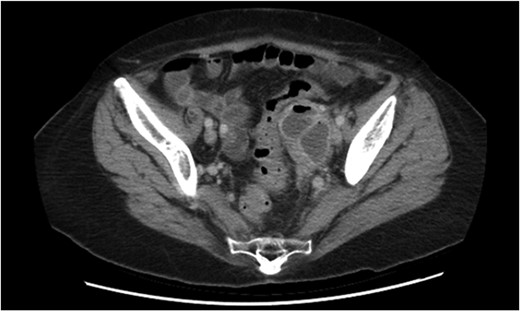

A 65-year-old woman was referred by her general practitioner to the gynaecology service of a metropolitan hospital with a 5-day history of abdominal pain lateralizing to the left iliac fossa, fevers, anorexia and diarrhoea. She was hemodynamically stable and the physical examination revealed marked tenderness to deep palpation and mild guarding in the left iliac fossa. Bimanual examination revealed an exquisitely tender and difficult to define adnexal mass. Her background history included a lower caesarean section, hyperlipidaemia and osteoporosis. No family history of malignancy was present. Interestingly, the initial contrast computed tomography (CT) abdomen and pelvis scan characterized a left tubular adnexal structure with an air fluid level but normal colon, and was reported as pyosalpingitis (Fig. 1). A subsequent pelvic ultrasound scan noted sigmoid thickening. Inflammatory markers were raised with a white cell count of 15.4 × 109 cells/L and CRP of 155 mg/L. Although initially afebrile, she spiked a temperature of 38.4 and commenced IV antibiotics for pelvic inflammatory disease. Given the uncommon presence of gas in the tubo-ovarian abscess and the suggestion of diverticulitis, a general surgical opinion was sought. It was agreed upon that this was most likely acute sigmoid diverticulitis complicated by a local perforation into the left salpingeal tube and ovary.

Initial CT demonstrating a gas containing the left adnexal mass and normal sigmoid colon.